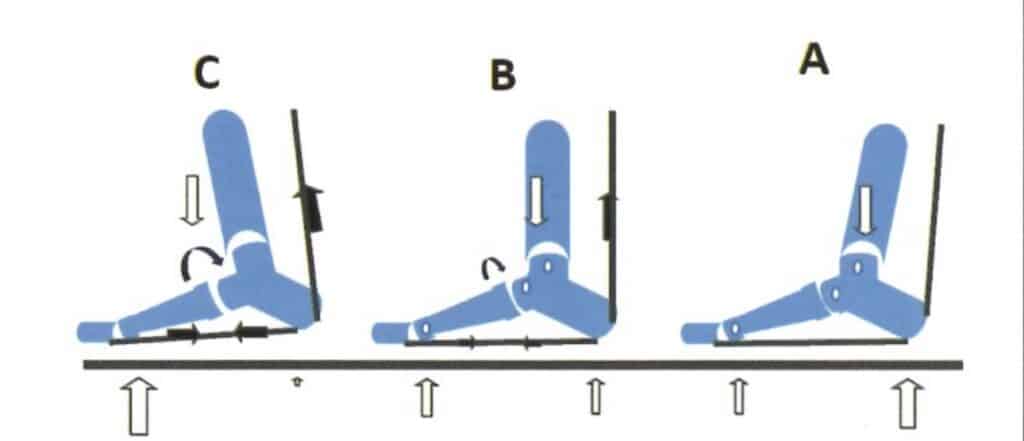

Ahora imagina que esa cuerda (el tendón de Aquiles) que une tus gemelos al talón está siempre tirante, siempre corta. ¿Qué ocurre? Tus gemelos acortados jalan del talón hacia arriba incluso cuando deberías apoyar el pie relajadamente. Es como si tus pantorrillas estuvieran diciendo todo el rato “¡eh, talón, arriba!”. Esto causa dos cosas principales en tu forma de pisar:

Tu talón no apoya bien: con gemelos muy tensos, puede que camines casi de puntillas sin darte cuenta, aunque lo más común es que levantes el talón antes de tiempo. El talón quiere levantarse pronto del suelo al caminar, porque los músculos tiran de él hacia arriba. Eso hace que pases más tiempo apoyando la parte delantera de tu pie donde las cabezas metatarsales. Más presión, durante más tiempo.

Tu pie se tensa por abajo: al tirar del talón hacia arriba, la planta del pie (especialmente una banda gruesa que tiene debajo llamada fascia plantar) se estira y se tensa como una goma elástica. Además, al no apoyar bien el talón, cargas más peso en la parte delantera del pie (el antepié). Es como si en vez de repartir el peso en todo el pie, estuvieras forzando más la parte de adelante.

Piensa en una cadena conectada desde tu pantorrilla hasta tus dedos del pie: el músculo de la pantorrilla tira del tendón de Aquiles, el tendón tira del talón, y a su vez el talón estira la fascia plantar (la banda bajo el pie) que llega hasta los dedos. Si tiras de un extremo de la cadena (la pantorrilla), todo lo demás se tensa. Por eso, un problema arriba puede sentirse abajo.